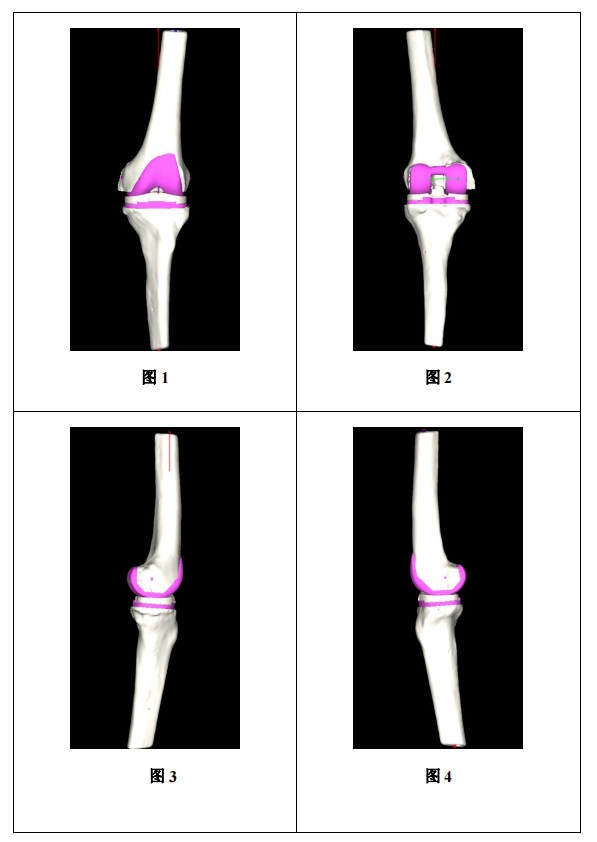

▲ 患者股骨远端三维视图

▲ 患者股骨髁三维视图

▲ 患者胫骨平台三维视图

骨科关节置换手术,术前精准手术方案的制定是手术成功与否的关键。手术前,钟达副教授运用人工智能系统根据患者术前三维CT扫描数据,快速实现三维重建解剖模型、智能分割、智能识别解剖位点,并根据股骨及胫骨的解剖形态,智能匹配最适假体型号及安放位置,实现个性化定制手术方案。

▲ 患者左膝规划结果